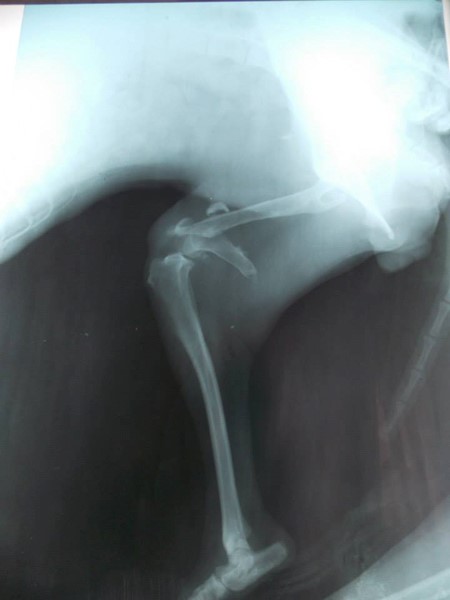

СНЦ Грижа и подслон за всеки, благодари на всички, които са се отзовали и са оказали финансова помощ за операциите на Вея в клиниката на Тракийския университет- събрани са 190 лв. , а операцията струва 300 лв. Остават неплатени още 110 лв. Операцията по премахването а болтовете и пироните от крачето на Вея беше миналата седмица в клиника в Русе, а дължимата сума за нея е 80 лв.